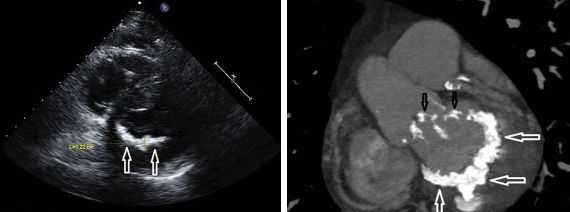

- Эхокардиография. При УЗИ оценивают сохранность сократительной и насосной функций, работу клапанов и наличие регургитации крови, давление в сердечных камерах. При исследовании у детей обнаруживаются признаки кардиомиопатии, врожденные пороки. Особенности кровотока изучаются с помощью допплерографии.

- ЭхоКГ. При УЗИ сердца обнаруживается гипертрофия стенок и расширение полости правого желудочка, наличие трикуспидальной регургитации, снижение показателя систолической экскурсии трикуспидального кольца (TASPE). Для уточнения данных выполняется трехмерная эхокардиография в режиме реального времени (RT3DE).

Другой важный инструментальный метод диагностики — эхокардиография (Эхо-КГ) . Эхо-КГ — это безболезненное ультразвуковое исследование, которое позволяет исследовать работу сердца в реальном времени. Эхокардиография покажет уменьшение эластичности клапана, его повреждение, размер отверстия митрального клапана и расстояние между его створками. Также при исследовании можно увидеть разрыв папиллярной мышцы и провисание клапанных створок в полость левого предсердия [4] [8] [9] .